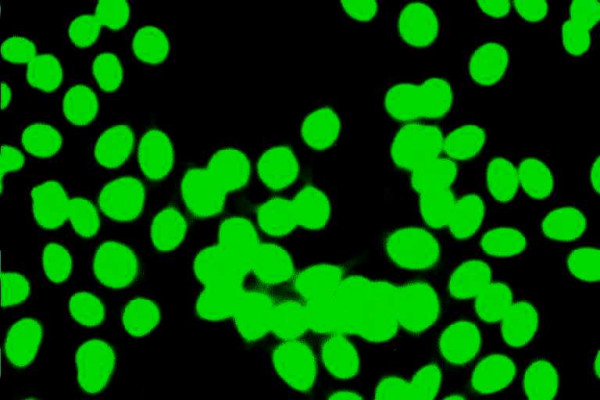

自身免疫性肝炎(AIH)是一种慢性肝脏坏死性炎症疾病,其特征是高丙种球蛋白血症、特征性自身抗体、与 HLA DR3 或 DR4 相关以及对免疫抑制治疗的良好反应。病因不明。在没有病毒、代谢、遗传和中毒性慢性肝炎或肝损伤病因的情况下,检测非器官和肝脏相关的自身抗体仍然是诊断该病的标志。本文报告了 AIH 目前的分类以及在该疾病中发现的几种自身抗体/目标自身抗原。此外,还阐述了这些标记物在鉴别诊断和 AIH 发病机制研究中的重要性。AIH 可细分为两大类型:AIH 1 型(AIH-1)和 AIH 2 型(AIH-2)。AIH-1 型的特征是检测到平滑肌自身抗体(SMA)和/或抗核抗体(ANA)。检测抗中性粒细胞胞浆自身抗体(ANCA)、抗淀粉样糖蛋白受体抗体(抗ASGP-R)和抗可溶性肝抗原或肝胰腺抗体(抗SLA/LP)可能有助于鉴别ANA/SMA血清阴性的患者。AIH-2的特点是存在针对肝脏和肾脏微粒体抗原的特异性自身抗体(抗LKM-1型或不常见的抗LKM-3型)和/或针对肝脏胞浆1抗原的自身抗体(抗LC1)。在一些慢性丙型肝炎(HCV)和慢性丁型肝炎(HDV)患者中也能检测到抗 LKM-1 和抗 LKM-3 自身抗体。细胞色素 P450 2D6 (CYP2D6) 已被证实是 AIH-2 和 HCV 感染中抗 LKM-1 自身抗体的主要靶抗原。最近有令人信服的数据表明,CYP2D6 在肝细胞表面的表达表明,抗 LKM-1 自身抗体在肝损伤中起着致病作用。UDP-糖醛酸转移酶家族 1 已被确定为抗 LKM-3 的靶自身抗原。因此,区分 AIH 和慢性病毒性肝炎(尤其是 HCV)尤为重要。最近,抗SLA/LP和抗LC1自身抗体的分子靶点被确定为一种50 kDa的UGA抑制tRNA相关蛋白和一种肝脏特异性酶--甲氨蝶呤环化酶。抗ASGP-R和抗LC1自身抗体似乎与疾病的严重程度和对治疗的反应密切相关,这表明这些自身抗体对肝细胞损伤具有致病作用。但一般来说,自身抗体不应被用于监测治疗、预测 AIH 的活动性或预后。最后,本文还介绍了一种特殊形式的 AIH,即自身免疫性多内分泌病-念珠菌病-外胚层营养不良综合征(APECED),它可能发生在一些患有罕见遗传综合征的患者身上。肝微粒体自身抗体(抗-LM)是在作为 APECED 疾病组成部分的 AIH 中检测到的特异性自身抗体,也可在二氢嗪诱发的肝炎病例中检测到。在与 APECED 相关的 AIH 和二氢嗪诱导的肝炎中,细胞色素 P450 1A2 被确定为抗 LM 自身抗体的靶自身抗原。后者可能表明,类似的自身免疫致病机制可导致易感个体的肝损伤,而与原发性缺陷无关。自身抗原-自身抗体复合物的特征描述仍然是一种极具吸引力的重要工具,可用于获得正确的诊断,并深入了解肝脏耐受性是如何被放弃以及 AIH 是如何产生的这一尚未解开的谜团。

Autoimmune hepatitis (AIH) is a chronic necroinflammatory disease of the liver characterized by hypergammaglobulinemia, characteristic autoantibodies, association with HLA DR3 or DR4 and a favorable response to immunosuppressive treatment. The etiology is unknown. The detection of non-organ and liver-related autoantibodies remains the hallmark for the diagnosis of the disease in the absence of viral, metabolic, genetic, and toxic etiology of chronic hepatitis or hepatic injury. The current classification of AIH and the several autoantibodies/target-autoantigens found in this disease are reported. Current aspects on the significance of these markers in the differential diagnosis and the study of pathogenesis of AIH are also stated. AIH is subdivided into two major types; AIH type 1 (AIH-1) and type 2 (AIH-2). AIH-1 is characterized by the detection of smooth muscle autoantibodies (SMA) and/or antinuclear antibodies (ANA). Determination of antineutrophil cytoplasmic autoantibodies (ANCA), antibodies against the asialoglycoprotein receptor (anti-ASGP-R) and antibodies against to soluble liver antigens or liver-pancreas (anti-SLA/LP) may be useful for the identification of patients who are seronegative for ANA/SMA. AIH-2 is characterized by the presence of specific autoantibodies against liver and kidney microsomal antigens (anti-LKM type 1 or infrequently anti-LKM type 3) and/or autoantibodies against liver cytosol 1 antigen (anti-LC1). Anti-LKM-1 and anti-LKM-3 autoantibodies are also detected in some patients with chronic hepatitis C (HCV) and chronic hepatitis D (HDV). Cytochrome P450 2D6 (CYP2D6) has been documented as the major target-autoantigen of anti-LKM-1 autoantibodies in both AIH-2 and HCV infection. Recent convincing data demonstrated the expression of CYP2D6 on the surface of hepatocytes suggesting a pathogenetic role of anti-LKM-1 autoantibodies for the liver damage. Family 1 of UDP-glycuronosyltransferases has been identified as the target-autoantigen of anti-LKM-3. For these reasons the distinction between AIH and chronic viral hepatitis (especially of HCV) is of particular importance. Recently, the molecular target of anti-SLA/LP and anti-LC1 autoantibodies were identified as a 50 kDa UGA-suppressor tRNA-associated protein and a liver specific enzyme, the formiminotransferase cyclodeaminase, respectively. Anti-ASGP-R and anti-LC1 autoantibodies appear to correlate closely with disease severity and response to treatment suggesting a pathogenetic role of these autoantibodies for the hepatocellular injury. In general however, autoantibodies should not be used to monitor treatment, predict AIH activity or outcome. Finally, the current aspects on a specific form of AIH that may develop in some patients with a rare genetic syndrome, the autoimmune polyendocrinopathy-candidiasis-ectodermal dystrophy syndrome (APECED) are also given. Autoantibodies against liver microsomes (anti-LM) are the specific autoantibodies detected in AIH as a disease component of APECED but also in cases of dihydralazine-induced hepatitis. Cytochrome P450 1A2 has been identified as the target-autoantigen of anti-LM autoantibodies in both APECED-related AIH and dihydralazine-induced hepatitis. The latter may indicate that similar autoimmune pathogenetic mechanisms can lead to liver injury in susceptible individuals irrespective of the primary defect. Characterization of the autoantigen-autoantibody repertoire continues to be an attractive and important tool to get access to the correct diagnosis and to gain insight into the as yet unresolved mystery of how hepatic tolerance is given up and AIH ensues.